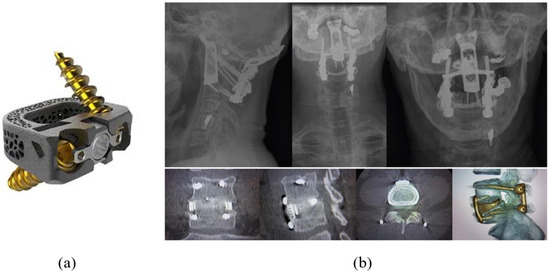

The integration of 3D printing technology has also revolutionized the field, allowing for the rapid, cost-effective customization of prosthetics tailored to individual needs. Not only does 3D printing expedite production, but it also reduces costs, making advanced prosthetics more accessible. Concurrently, neural interface technology is advancing toward connecting prosthetic devices directly with the nervous system to provide sensory feedback. Although still in its developmental stages, this technology holds the potential to revolutionize prosthetics by allowing users to experience sensation through their devices, bringing them closer to full integration between humans and machines. One of the first 3D-printed prostheses to make a big impact was made by Anatomics, an Australian medical device manufacturer, in late 2015, and a medical team led by neurosurgeon Ralph Mobbs successfully implanted two 3D-printed artificial vertebrae in a patient (Figure 3).